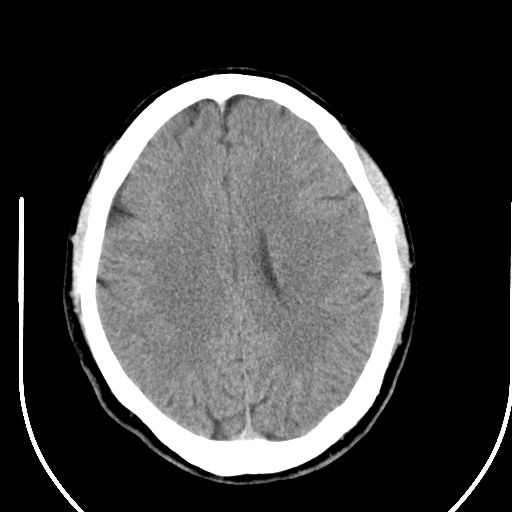

标题: CT25423:头部外伤意外发现右顶叶??? [打印本页]

标题: CT25423:头部外伤意外发现右顶叶???

ct值约13hu。

边缘清晰,没有占位效应,不像脑沟,结合ct值,软化灶可能吧

与脑沟没关系,小软化灶或陈旧性感染吧!

看样年纪不小了直接报腔梗,当然你要想报软化灶也是一样的

考虑右侧额叶巨腔隙灶;建议必要时行mri检查。